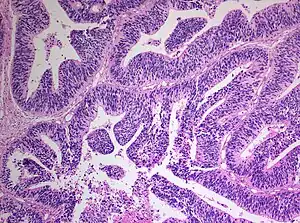

Histology of Medulloepithelioma

The World Health Organization has classified the central nervous system primitive neuroectodermal tumors into five subtypes: neuroblastoma, ganglioneuroblastoma, medulloepithelioma, ependymoblastoma, and not otherwise specified PNET.[1] The last one encompasses the PNETs with varying characteristics that hasn't been well defined yet.[1] Neuroblastomas are PNETS that involve the process of cell differentiation into neurons,[1][2] while ganglioneuroblastomas are PNETs that involve ganglion cells.[1]

Medulloepithelioma, on the other hand, are tumors involving the constant cell division on the epithelium tissue where bundle of neuron endings are located.[1] Such tissue will differentiate into a similar form as the embryonic neural tube, also known as the starting structure of the central nervous system.[1][2][3] Medulloepitheliomas also present a pattern known as rosettes, characterized by the arrangement of a bundle of cells into circular shapes and around a center or a neuropil.[1] Ependymoblastoma also present rosettes as well as a higher density of cells.[1][3] It involves the process of differentiation into ependymal cells.[2][3]